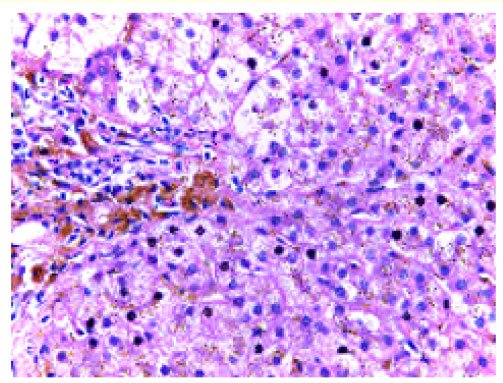

Recent Update in Diagnostic Evaluation of Hereditary Hemochromatosis

Jeevan Divakaran, Ila Chauhan, Jigar Katwala and Kandamaran Krishnamurthy. 12(7): 72-81.